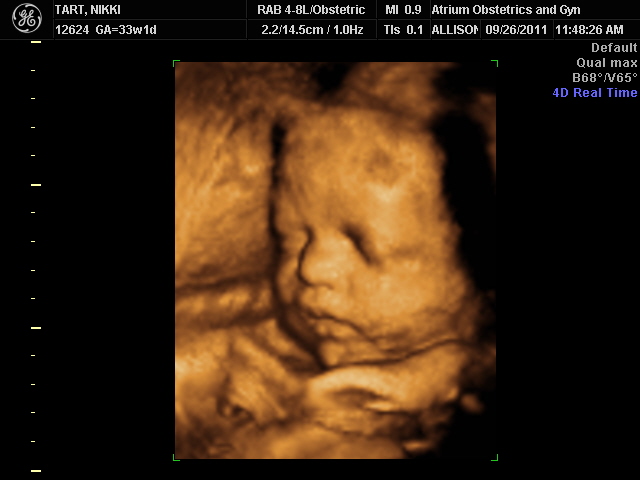

My baby in 3D at 33 weeks. The baby is head down, with their face facing your back. Your baby will continue to pack on the pounds as your due date approaches.

This 4-D pregnancy ultrasound video shows baby at 33 weeks.During this stage of pregnancy, your baby gains about half a pound per week. Baby Weight and Baby Movement During 34 Week Pregnancy. The baby fattens up outside the womb for survival.

33 weeks pregnant ultrasound If you're having an ultrasound in your 33rd week of pregnancy, you will see that your baby is keeping his or her eyes open while being awake. In this image, the red and blue show blood flow to the part of his brain that lets the two halves of the brain communicate. He seems like a relative heavy weight at four and a half pounds, but remember, he could double that weight in the coming weeks.

The body of the baby starts filling up with the layers of fat that helps the baby to regulate the temperature of its body. 33 Week 3D Ultrasound Baby Picture. She really quickly spat out the weight - 2lbs 9oz - and moved on very quickly while I felt like a ton of bricks hit me.

The majority of our pregnant moms come for this particular baby ultrasound right around that 32-week mark. But those steroid shots they gave me (just in case baby was trying to make her appearance that early) worked wonders because at my appointment not even a full week later, I could see her completing breathing movements on her own. 33 Week 3D Ultrasound Pictures Pregnancy Baby Images 4D.